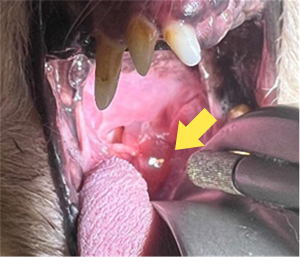

唾液腺嚢胞

これが空気の流れを悪くして、気管虚脱を悪化させていました。

嚢胞と唾液腺の切除後は喉の違和感はなくなり、咳も落ち着きました。

気管虚脱はワンちゃんで多く見られる疾患ですが、このように原因が別にある事もあります。